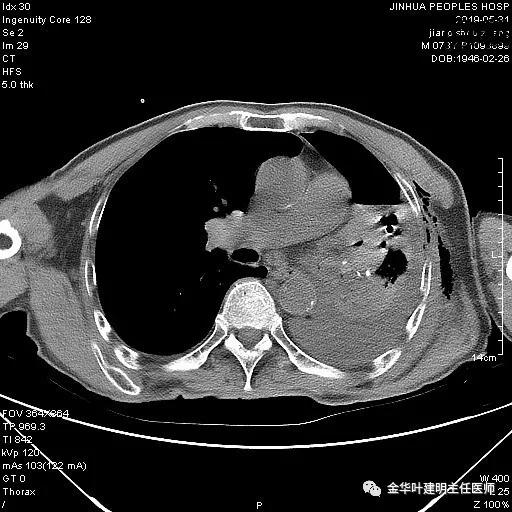

考虑左侧大量胸腔积液,遂进一步胸部CT检查:

以上是肺窗表现,下面为纵隔窗影像:

因为引流出的胸液为血性,但感觉不是特别鲜,查血色素9.5 g/L,术前是12.7g/L。当时考虑胸腔内出血可能,较为纠结的是是否需要进胸探查。但鉴于血压正常、心率不快,一般情况良好,不似胸内大出血休克的表现,所以仍想继续观察保守治疗。